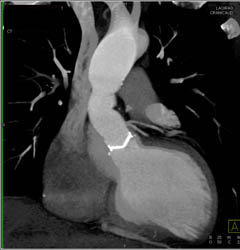

Left Atrial Thrombus